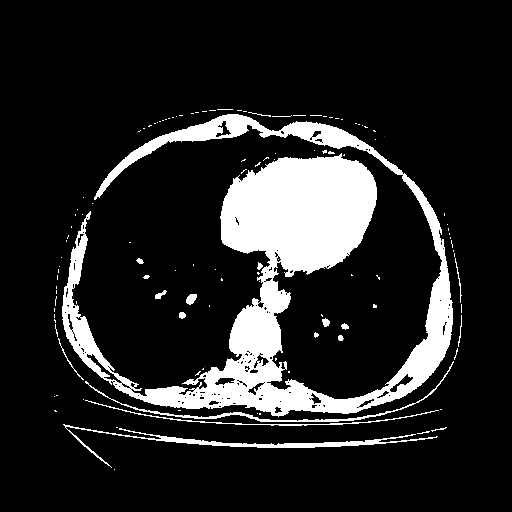

Image Grid

4Γ—3 grid: Rows show different image types (Original NATIVE, Reconstructed NATIVE, Original VENOUS, Generated VENOUS), Columns show windowing techniques (No Window, Lung Window, Mediastinum Window)

Original NATIVE CT scan (input)

Full window (WL 1023.5, WW 4095 β†’ Low βˆ’1024, High +3071)

Actual HU range: [-1024.0, 3071.0]